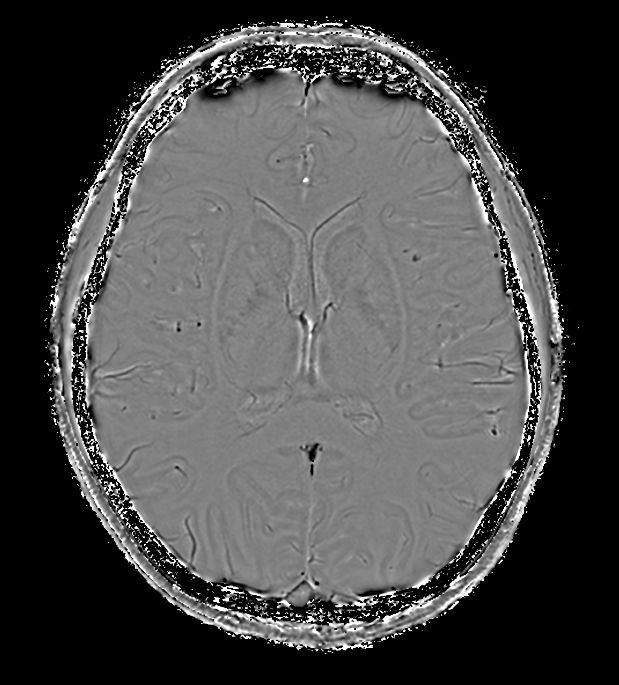

3D T1w TFE (Axial reformat)

-

3D Double IR (Axial reformat)